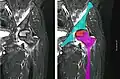

La mayoría de las veces los doctores ortopédicos diagnostican la enfermedad excepto en la mandíbula, donde normalmente es diagnosticado y tratado por cirujanos dentales y maxilofaciales. El examen de elección es la resonancia magnética, capaz de detectar osteonecrosis antes de que haya daño significativo en el hueso.

Radiografía de una osteonecrosis de la cabeza femoral izquierda. Hombre de 45 años de edad con SIDA. -

Resonancia magnética nuclear de una osteonecrosis de la cabeza femoral izquierda. Hombre de 45 años de edad con SIDA.